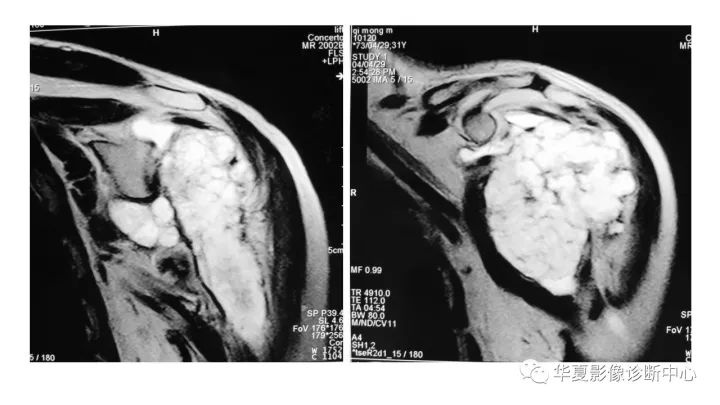

肱骨上段软骨肉瘤1例X线CT及MR影像表现

【病例】肱骨上段软骨肉瘤1例X线CT及MR影像表现